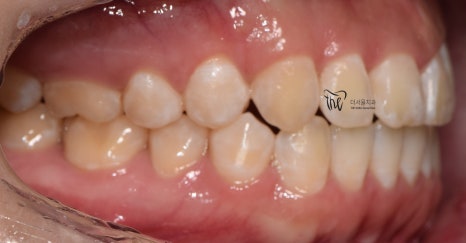

『치료 종료』

그리고, 다른 환자들과는 다르게

정기검진을 할 필요가 없었죠?

매일 보니깐요.

즉, 저와 늘상 가깝게 지내면서 치열의

변화를 같이 지켜봤으며 인비절라인

치아교정 치료를 이어나간 결과

이제 윗니가 아랫니를 겹치게 덮는 모양이

나오게 되면서 치료를 끝마치게 되었네요.

물론, 해당 교합관계는 재발이 잘 되기 때문에

시간이 오래 흘렀을 때도, 꾸준히 검진을

받으면서 관리를 받아야 됩니다.

그러면서, 어느 단계에서부터 턱관절 통증 및

뻐근함이 거의 다 사라졌다는..

이것은, 두마리 토끼를 같이 잡았다.^^